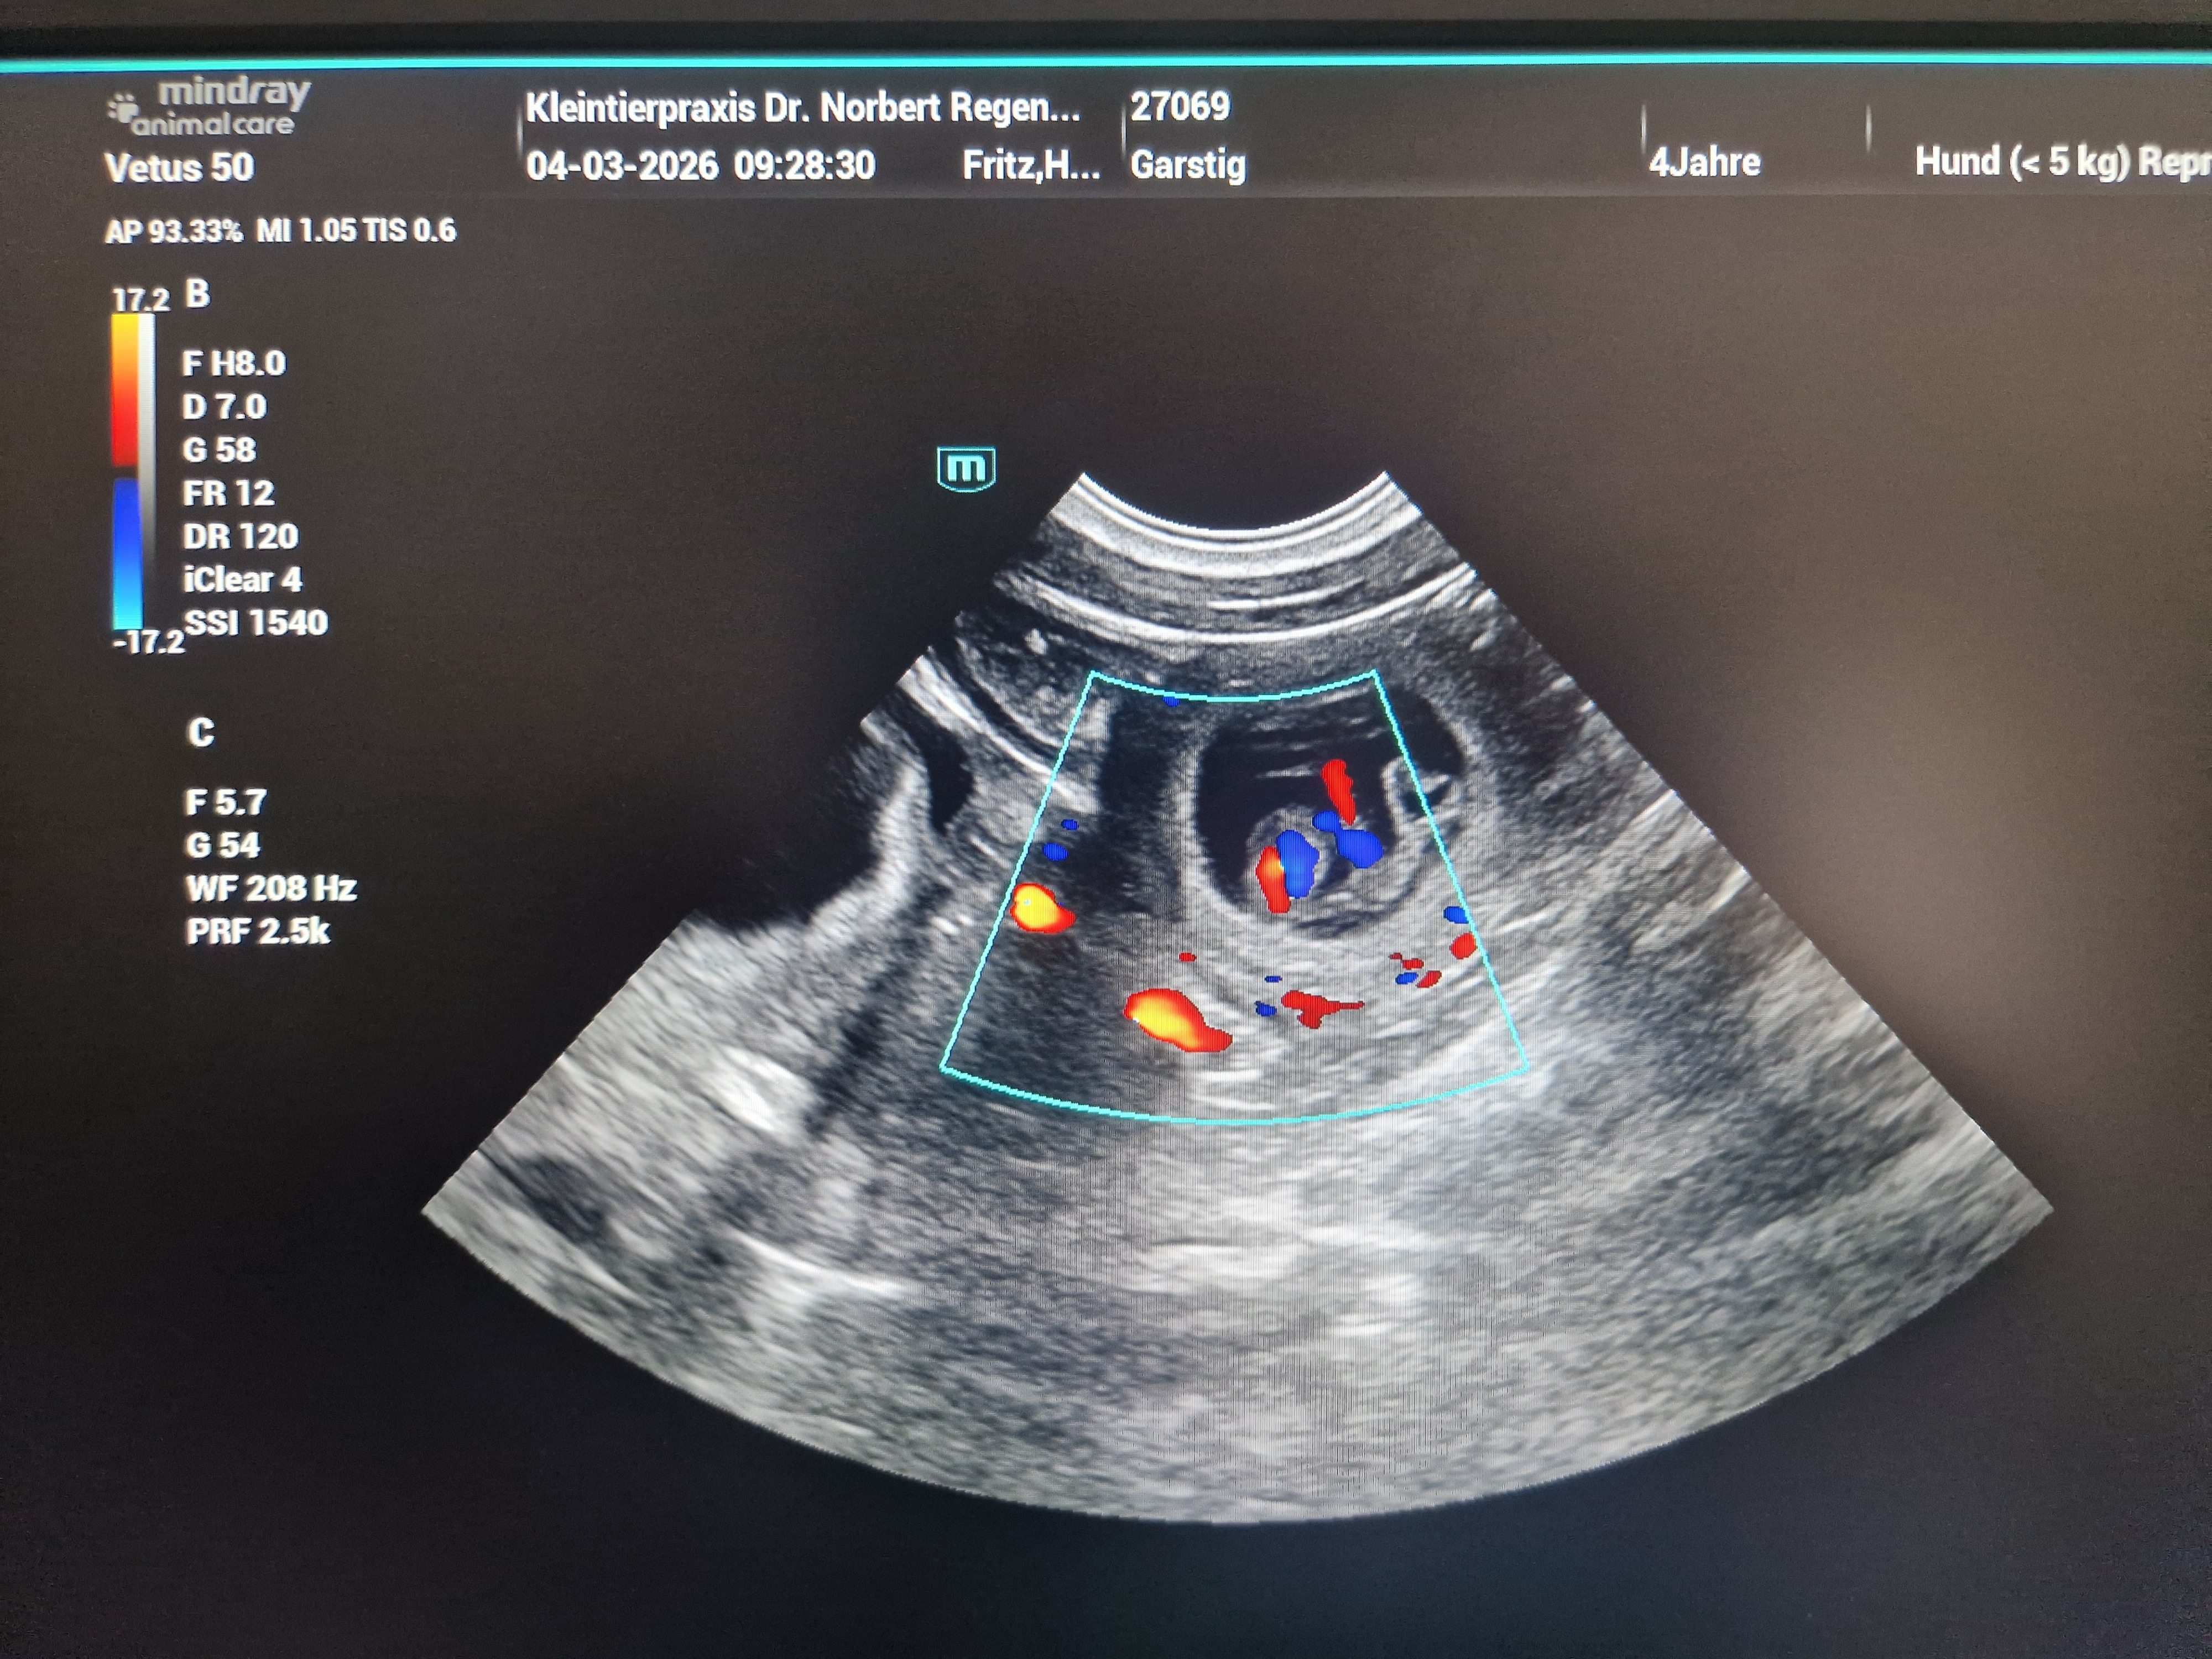

(04.03.2026) Yeaahhhh! Wir sind "schwanger"!

Heute haben wir es schwarz auf weiß und auch ein wenig bunt bekommen:

Garstig ist trächtig!!!

Der Tierarzt konnte 6 - 8 Welpen schallen, aber wie viele Welpen genau "drin" sind, werden wir erst erfahren, wenn sie ausziehen!

Beim Ultraschall ist es immer schwierig, da die Fruchthüllen ständig etwas hin- und herwabern. Und da ich meine Hündin nicht röntgen werde, müssen wir bis zum Auszug warten! :-)